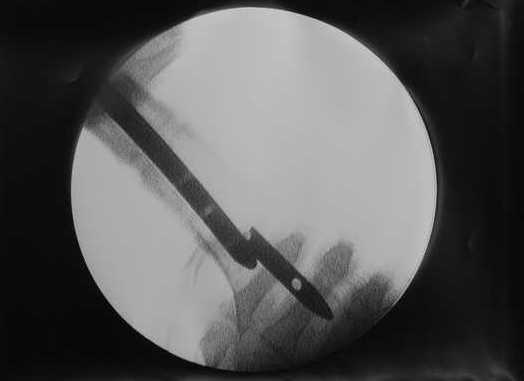

> Очень было бы любопытно посмотреть поэтапные Р-снимки с ЭОПа (хотя

В приложении пример, как их использовали после остеотомии бедра по поводу сросшегося с вальгусом перелома, чтобы не дать гвоздю уйти во внутренний мыщелок.